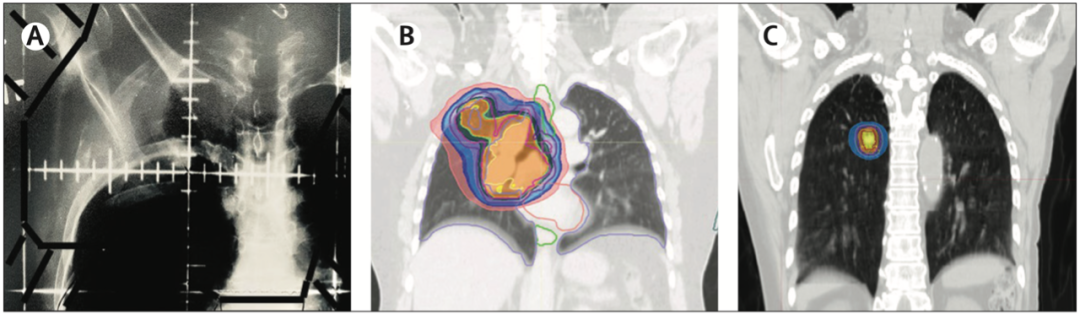

放疗从二维到立体定向放射治疗的演变

新型放疗技术举例

低分割、立体定向放射治疗或立体定向体部放射治疗(SBRT)最初是用于治疗颅内肿瘤,现在已经应用于多个身体部位,包括胸部、胃肠、泌尿生殖系统和骨骼等。SBRT也被称为立体定向消融放疗,其特点是将消融剂量的能量传递给肿瘤。这些新技术的作用随着系统治疗的发展而不断增加。